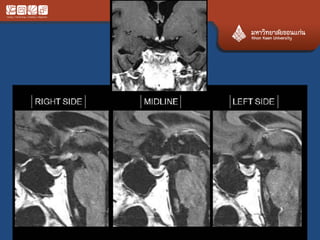

# chordoma

• Locally agreesive never metas

• Clivus, upper C, lower L, sacrum

• 70% at the midline

• Expansile, calcification, bright T2

• Ddx chondrosarcoma